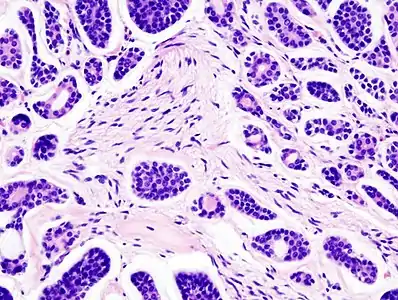

Micrograph of an adenoid cystic carcinoma of a salivary gland (right of image): Normal serous glands, typical of the parotid gland, are also seen (left of image), H&E stain. | |

- Histopathological image of adenoid cystic carcinoma of the salivary gland infiltrating a nerve (center), H&E stain